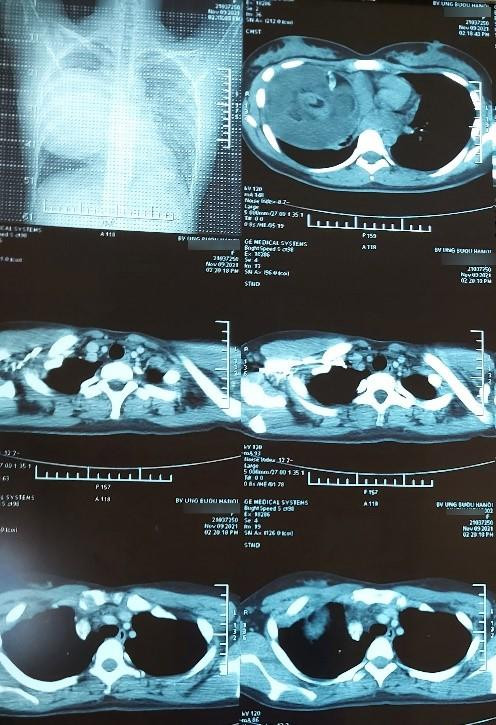

Tuy nhiên, một bệnh nhân nữ 19 tuổi ở Phú Xuyên – Hà Nội lại được phát hiện có u quái nằm trong lồng ngực gây tức ngực, khó thở. Đặc biệt, kích thước u rất lớn với đường kính khoảng 20 cm nên phẫu thuật tương đối phức tạp.

| Phim chụp trước và sau phẫu thuật của bệnh nhân |

TS.BS. Phan Lê Thắng – Trưởng khoa Ngoại Theo yêu cầu cho biết, vị trí u nằm ở trung thất trước trên bên phải, tổ chức u có cả lông, tóc, mỡ, xương. Khối u to, đè đẩy tim, chèn ép làm xẹp phổi, dính nhiều cơ quan nội tạng xung quanh. Phẫu thuật thành công đã giúp giải phóng khối u khỏi cơ thể, nở phổi giúp tăng diện tích thở cho bệnh nhân, quan trọng hơn là tránh được những biến chứng nặng sau này về tuần hoàn và tim mạch nếu để u tiếp tục phát triển.